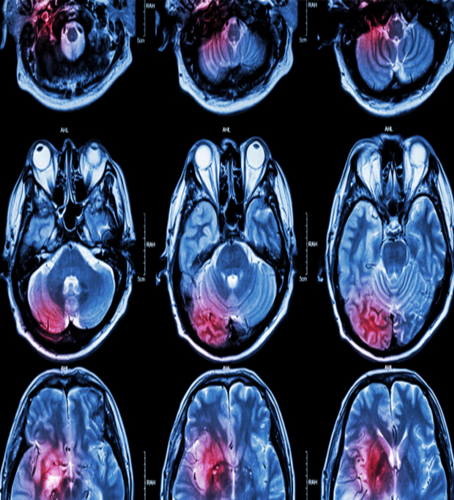

Neuroimaging and Advanced Techniques

Neuroimaging plays a crucial role in terms of determining the nature of the lesions and vascular peculiarities associated with cognitive deficiency. The modality of choice of imaging studies is MRI because it is sensitive in the detection of cortical and subcortical infarcts, white matter hyperintensities, and hippocampal atrophy [21].

* Structural MRI: Reveals strategic infarcts (e.g., thalamus, medial temporal lobe).

* Diffusion Tensor Imaging (DTI): Assesses white matter integrity and tract disruption.

* Functional MRI (fMRI): Looks at the connection between brain networks, particularly during research.

Certainly, in other situations, the CT scan can be employed acutely; however, it is less sensitive to changes occurring in the brain with regard to cognition.

Figure 1